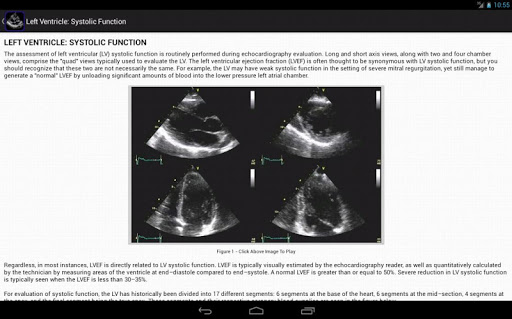

Left Ventricle: Systolic Function

EchoSource provides a detailed overview of clinical disorders and their evaluation using echocardiography, incorporating educational figures and videos as well as reviews of pertinent medical literature. Whether you are a beginner just learning standard echocardiography imaging views, or a practicing clinician needing a quick reference to guideline-based echocardiographic criteria for diagnosing the severity of valvular heart disease, EchoSource is the ideal application to assist you.